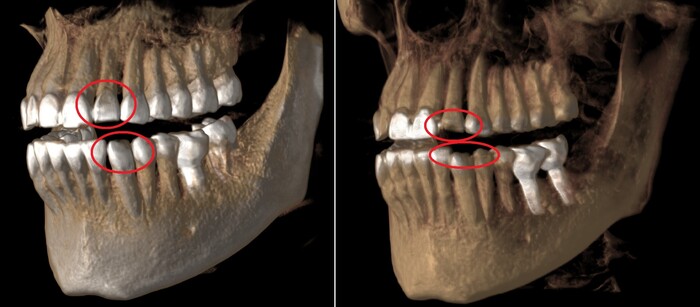

Есть такое понятие, как клыковое ведение (или клыковая дезокклюзия) – это разобщение задних зубов во время боковых движений нижней челюсти. Иными словами, (прочтите медленно) при смещении нижней челюсти в сторону, двигаясь клыком нижней челюсти по клыку верхней челюсти на момент контакта бугров, у боковых зубов не должно быть контакта. В данном случае он есть именно на 7ках:

Оранжевым цветом отмечена стираемость зубов, а красным место контакта.

Зубы стерлись, высота прикуса занизилась. В связи с чем появился преждевременный контакт керамической коронки на нижнем 7м зубе (керамика не стирается) и верхним 7м зубом.

(Вы можете отметить, что на 6ке тоже керамическая коронка. Не стоит забывать, что ее переделывали. Следовательно, она была подогнана под истертые зубы).

Поэтому, из-за постоянной перегрузки винт и сломался. Могучий Иван снова достал винт, заменил его на новый и прикрутил обратно ту же самую коронку. Подточил 7й зуб, вывив его из преждевременного контакта с нижним. (снимки сделаны при помощи зеркала) на 3,4,5,6 зубах отпечатана копирка, на 7м нет: